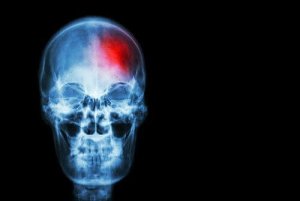

Om het simpel te zeggen, een beroerte is het verlies van bloedcirculatie naar de hersenen.

Het risico wordt hoger als de hersenen langer zonder zuurstof zitten door het gebrek aan bloeddoorstroming.